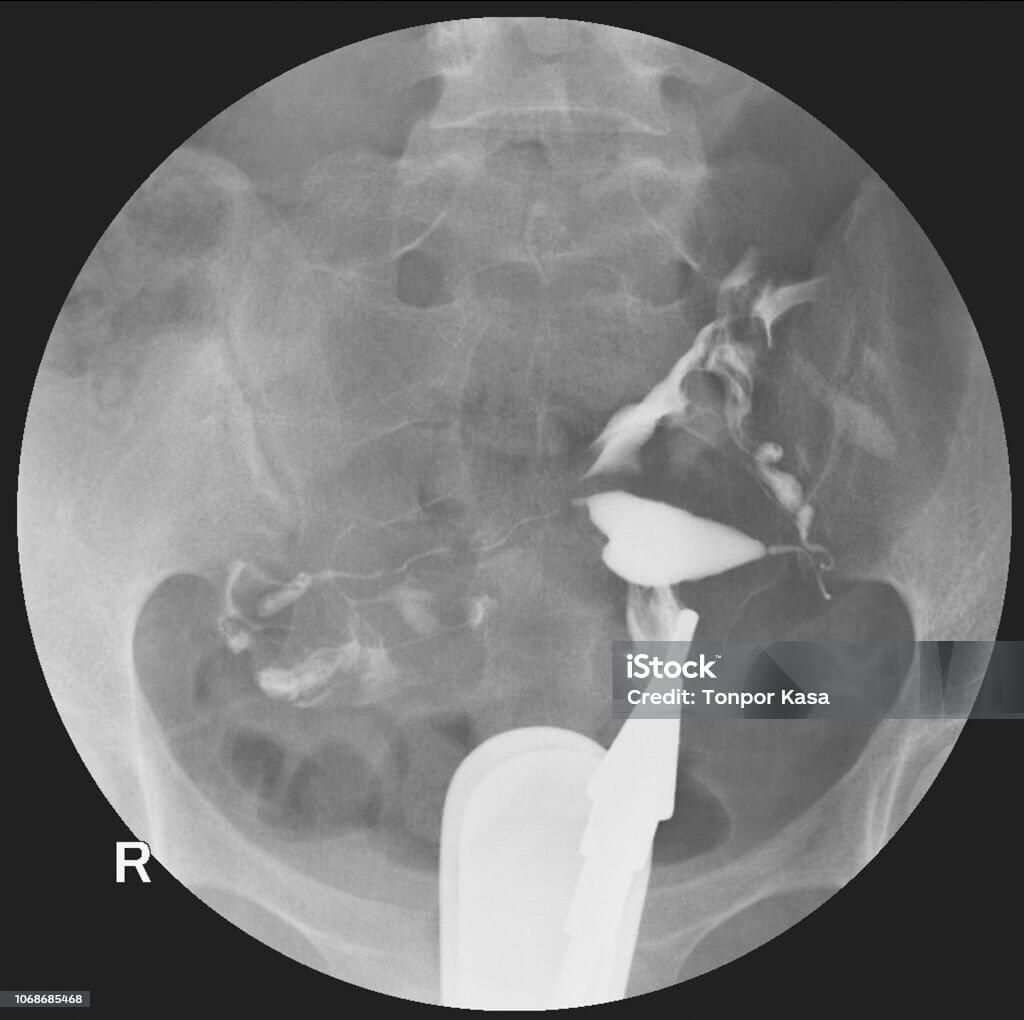

L’hystérosalpingographie est un examen d’imagerie qui permet de visualiser l’intérieur de l’utérus et des trompes de Fallope. Pour cela, un produit iodé, visible aux rayons X, est introduit dans l’utérus. Ce produit parcourt les trompes et permet de confirmer si le passage du liquide se fait normalement.

Pensez à un colorant injecté dans un conduit : si le liquide circule sans encombre, les trompes sont ouvertes. Un blocage indique des trompes obstruées. Cette méthode est essentielle pour détecter d’éventuelles anomalies impliquées dans les cas d’infertilité ou de fausses couches itératives.

Le radiologue interprète les résultats en observant comment le produit parcourt l’utérus et les trompes, et s’il atteint la cavité abdominale.

• Liquide passe des deux côtés : Tout est normal, la fertilité mécanique est préservée.

• Liquide bloqué d’un côté : Une trompe obstruée, potentiellement réductrice de fertilité.

• Liquide bloqué des deux côtés : Obstruction bilatérale des trompes, complexifiant la conception naturelle.

• Cavité irrégulière : Eventuelle anomalie utérine devant être explorée.